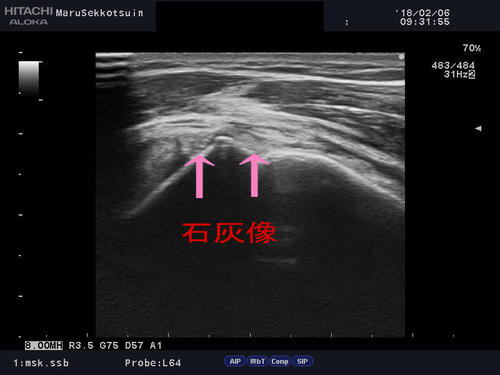

急に腕が上がらなくなった・・・「石灰沈着性腱板炎」

肩の筋肉内に沈着したリン酸カルシウム結晶(石灰)によって

原因不明で突然、炎症が生じて肩の痛みで動かせる範囲が狭くなる状態です。

石灰は身体のどの部位でも出来て、急に筋肉内に沈着して痛みを誘発する場合や、

以前から沈着していた石灰が刺激を受けて痛みを生じる場合もあります。